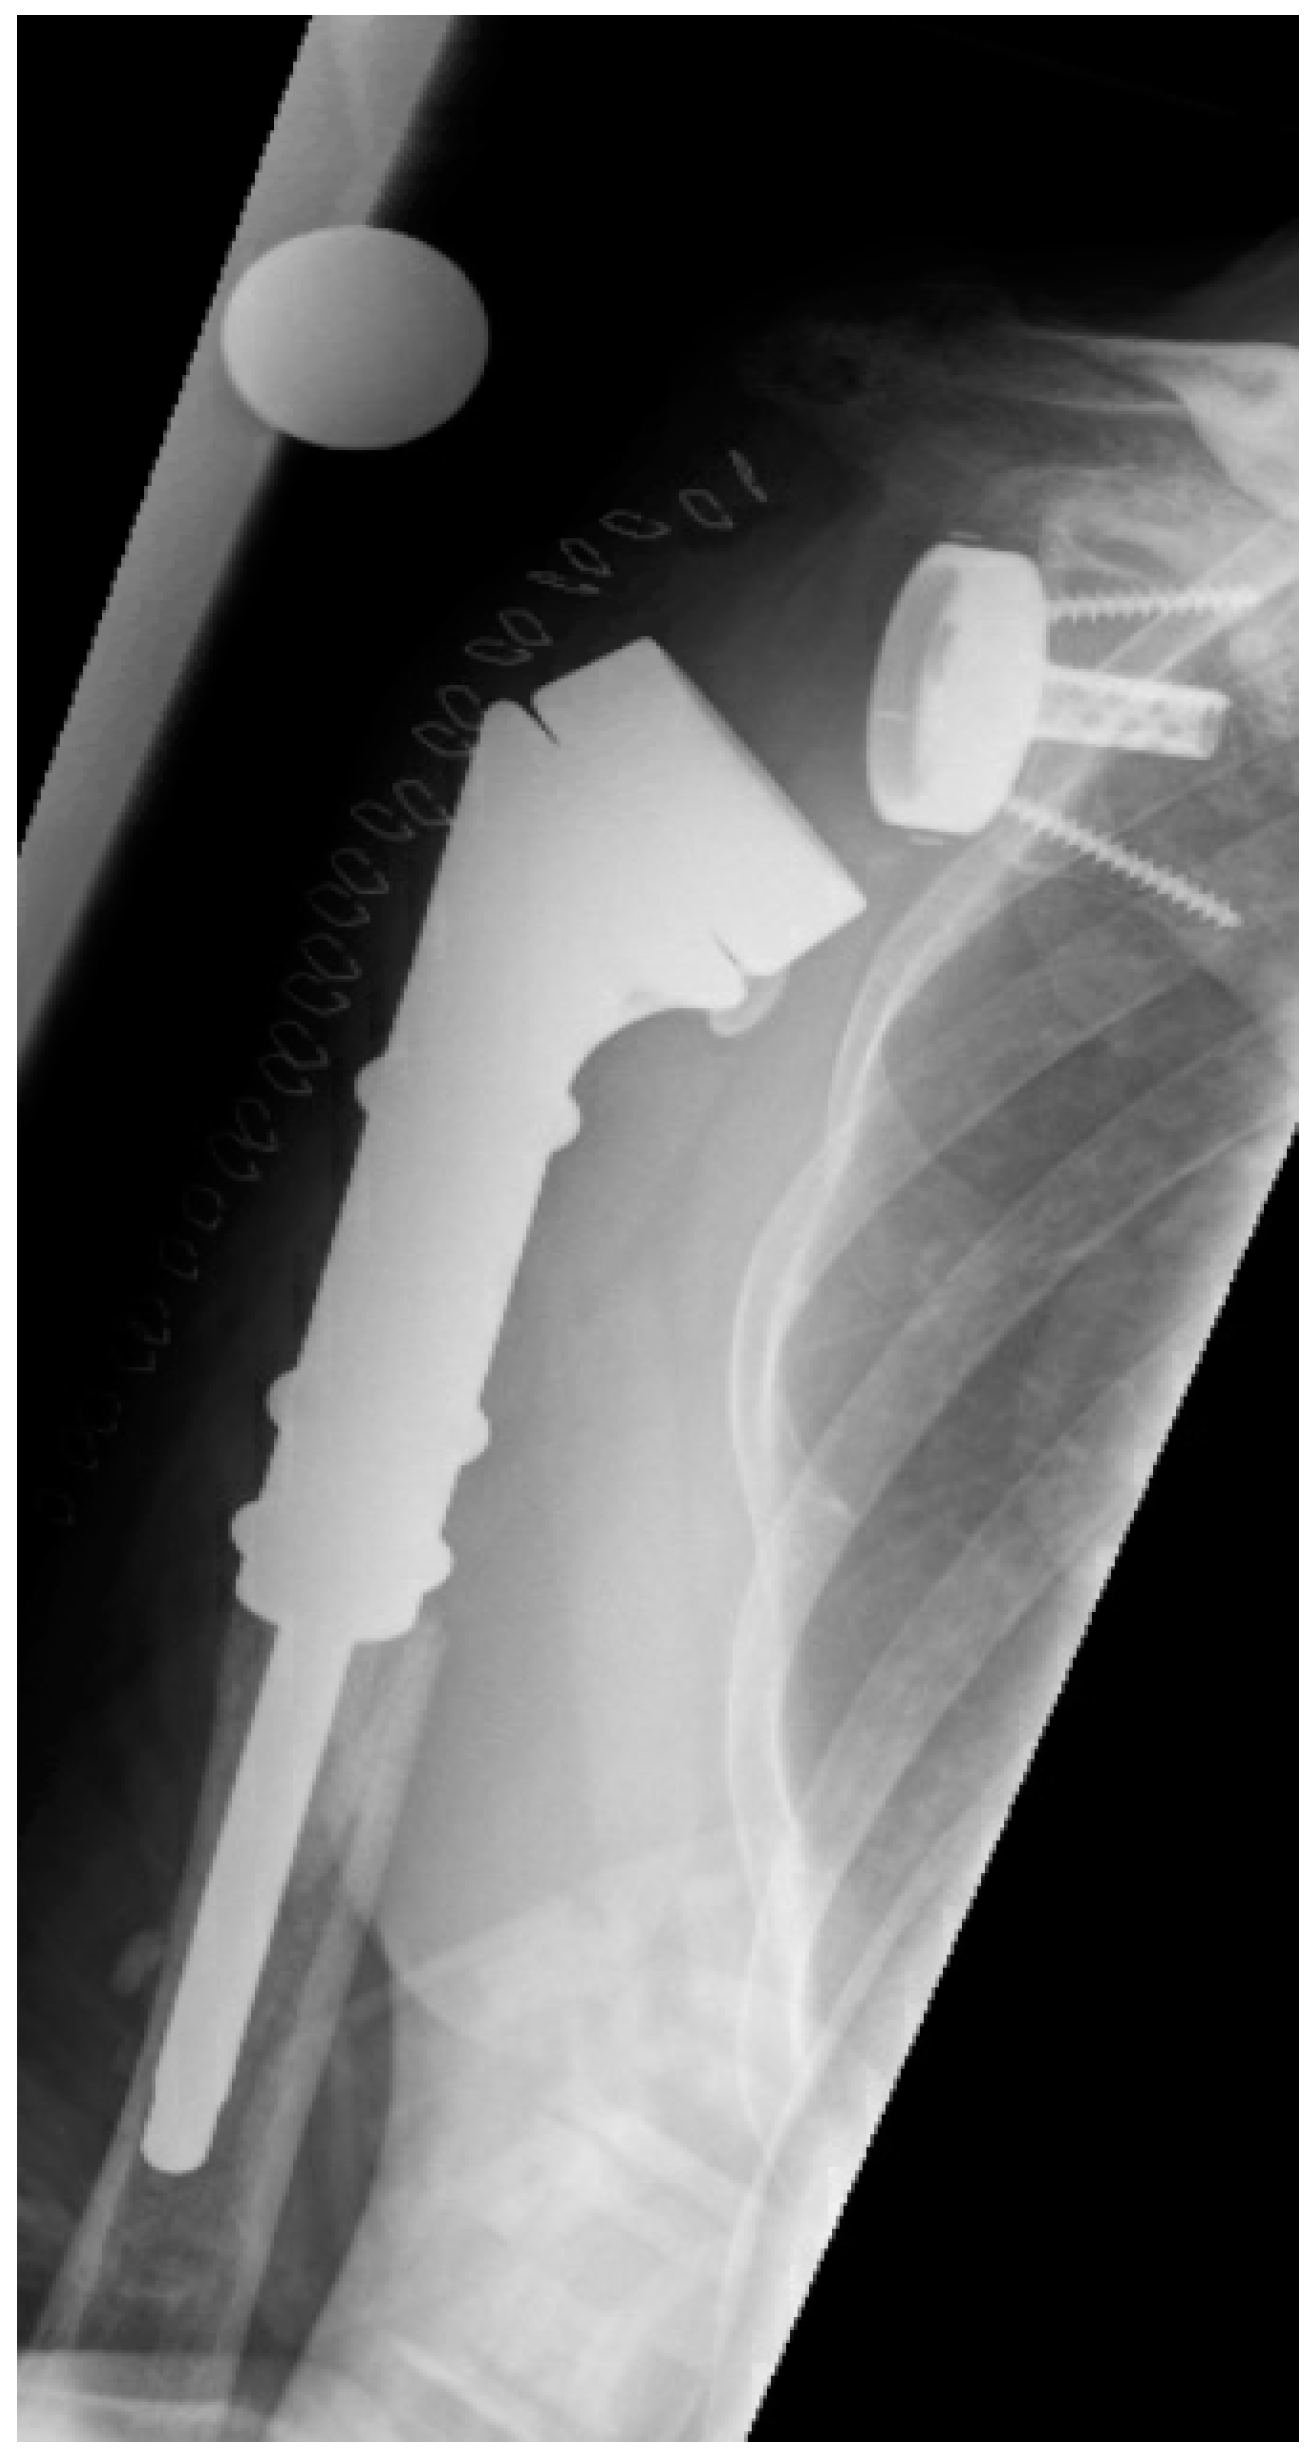

| Reimplanted prostheses | |

| RSA (n) | 9 (56%) |

| HA with CTA head (n) | 3 (19%) |

| Reverse proximal humeral replacement (n) | 4 (25%) |

| Explanted stem cemented (n) | 7 |

| Explanted stem uncemented (n) | 9 |

| Cemented stem for replantation (n) | 10 |

| Uncemented stem for replantation (n) | 6 |